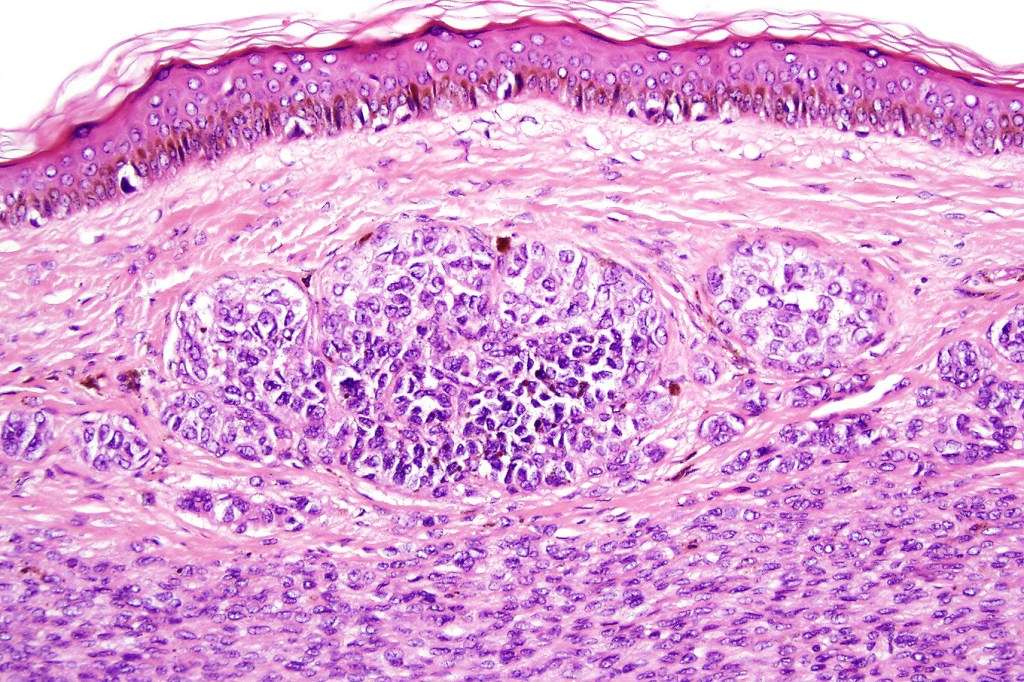

Histological features

•The nodule generally merges with the adjacent nevus but sometimes it can be sharply circumscribed

•It is hypercellular and most often composed of epithelioid cells showing little pleomorphism & only occasional mitoses

•Nuleoli are small

•Intracytoplasmic pseudo-inclusions

•The constituent cells are generally larger than the adjacent nevus cells

•Some examples show more marked pleomorphism with prominent nucleoli and increased mitotic activity but abnormal mitoses are not a feature. These are not associated with any sinister biological potential

•Absence of necrosis, hemorrhage or Pagetoid spread in the overlying epidermis

•Spindle cell, small blue cell, blue nevus-like features, Spitzoid & proliferative nodules with mesenchymal differentiation (myofibroblastic, chondroid & osteoid) can be seen